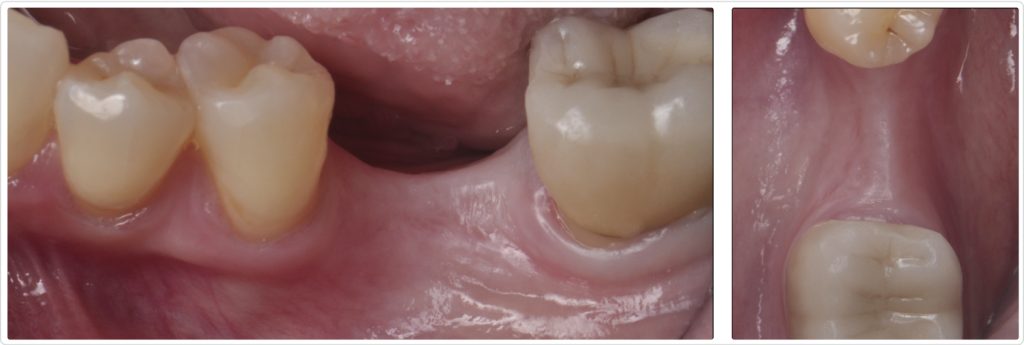

The patient, a 55-year-old woman with no significant medical history, presented with an edentulous site in the mandibular first molar region (area #19). The tooth had been extracted more than three years ago because of caries. Initial clinical examination (Figs. 1a and 1b) revealed a horizontal ridge defect and minimal keratinized mucosa at the site, posing challenges for implant placement and long-term stability.